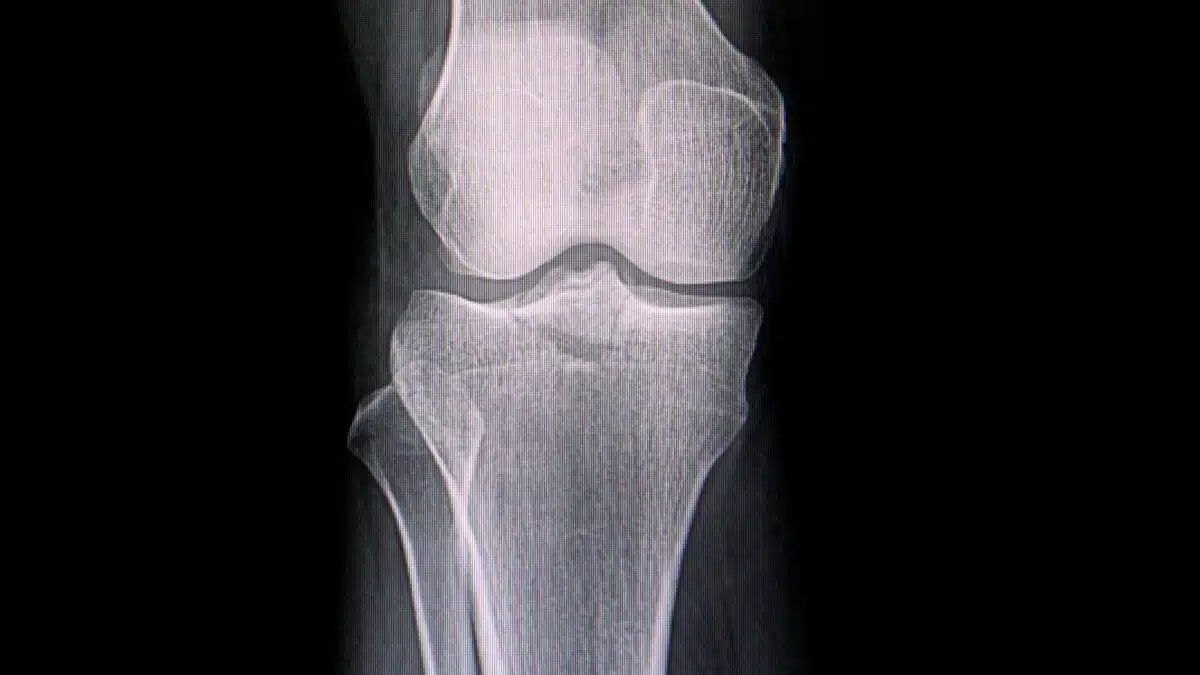

Frattura del piatto tibiale cos’è e come rimediare Fisioterapia e Logopedia benessere e postura

Frattura del piatto tibiale FisioScience